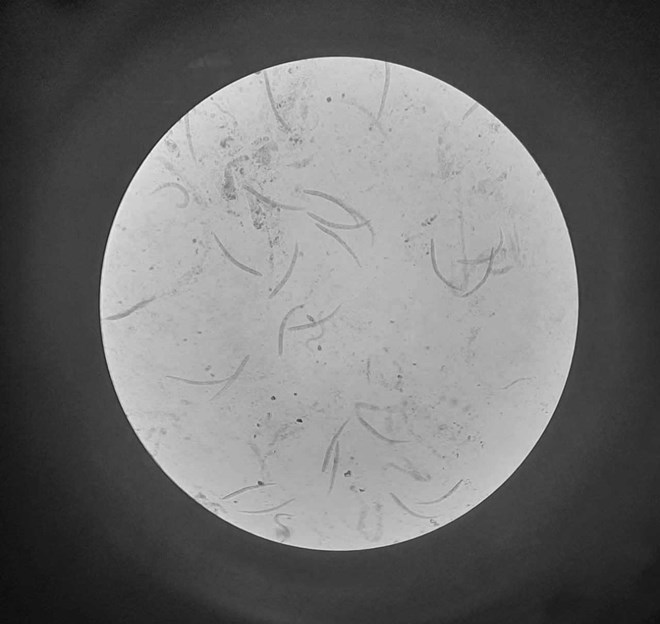

Hình ảnh giun lươn trong cơ thể người bệnh. Ảnh: BVCC

Tại bệnh viện, bệnh nhân được chẩn đoán suy gan cấp, rối loạn đông máu, K đại tràng. Xét nghiệm dịch dạ dày và dịch phế quản bệnh nhân có nhiều hình ảnh giun lươn, phù hợp bệnh cảnh lâm sàng, qua đó được chẩn đoán: Nhiễm giun lươn lan tỏa.

Theo bác sĩ Đặng Văn Dương - khoa Hồi sức tích cực, bệnh nhân đang trong quá trình điều trị bệnh nền nặng. Khi bệnh nhân chuyển đến với tình trạng nhiễm trùng nặng, các bác sĩ đã đánh giá bệnh nhân có nguy cơ nhiễm giun lươn lan tỏa và tiến hành xét nghiệm tìm kiếm. Khi có kết quả xét nghiệm dịch dạ dày và dịch phế quản ra giun lươn, bệnh nhân được khởi động ngay thuốc điều trị giun lươn đặc hiệu kết hợp với kháng sinh phổ rộng.